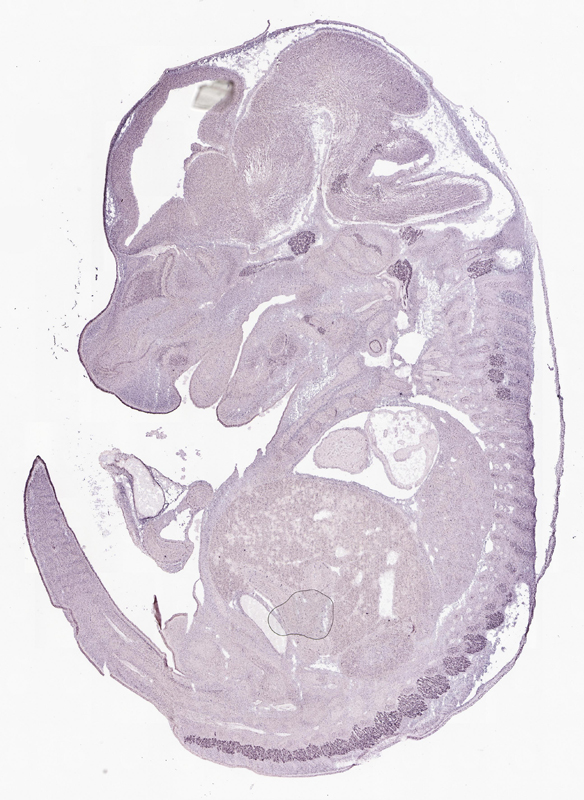

Reference: J:153498 Diez-Roux G, et al., A high-resolution anatomical atlas of the transcriptome in the mouse embryo. PLoS Biol. 2011;9(1):e1000582

Assay type: RNA in situ

Gene symbol: Atp6v0d1

Gene name: ATPase, H+ transporting, lysosomal V0 subunit D1

Probe: IMAGE clone 1907604

Probe preparation: Antisense labelled with digoxigenin RNA

Visualized with: Alkaline phosphatase

Assay notes: Cryosections of fresh frozen material were fixed in 4% paraformaldehyde for 20 min. before further processing. A tyramide-biotin/streptavidin amplification step was included in the in situ hybridization procedure.

Specimen euxassay_000642_01: embryonic day 14.5 (more )